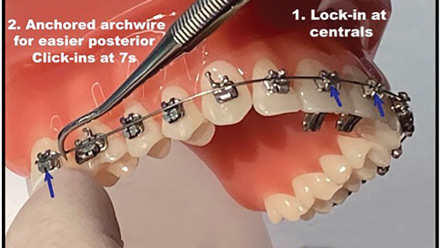

The 411 on 911s in Orthodontic Treatments

Abstract Orthodontic treatments can seem overwhelming, burdensome, and uncomfortable for patients, parents, and – when it comes to emergency visits – for orthodontists as well. As we evolve the industry, we must keep the patient’s experience top of mind and put them in the driver’s seat. In her article, Dr. Sima Yakoby Epstein, Founder and CEO of … Read more